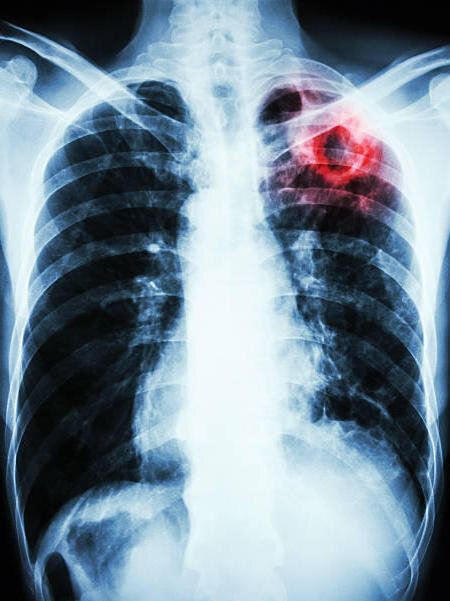

Симптомы открытой формы туберкулеза не только ярко выражены клинически, но также имеет лабораторные и рентгенологические признаки.

Основным методом диагностики является рентген. Это быстрое и доступное исследование. При этом будет виден очаг, который на снимке затемнен, еще будут каверны разных размеров и усиление рисунка легочной ткани.

Основным методом диагностики является рентген. Это быстрое и доступное исследование. При этом будет виден очаг, который на снимке затемнен, еще будут каверны разных размеров и усиление рисунка легочной ткани. К исследованиям, проводимым непосредтсвенно на человеке относится проба Манту, при которой подкожно вводится туберкулин. Если папула после введения увеличивается на 0,5 см, то это означает, что произошло инфицирование. Однако, это верно при условии, что год назад проба Манту показала отрицательный результат.